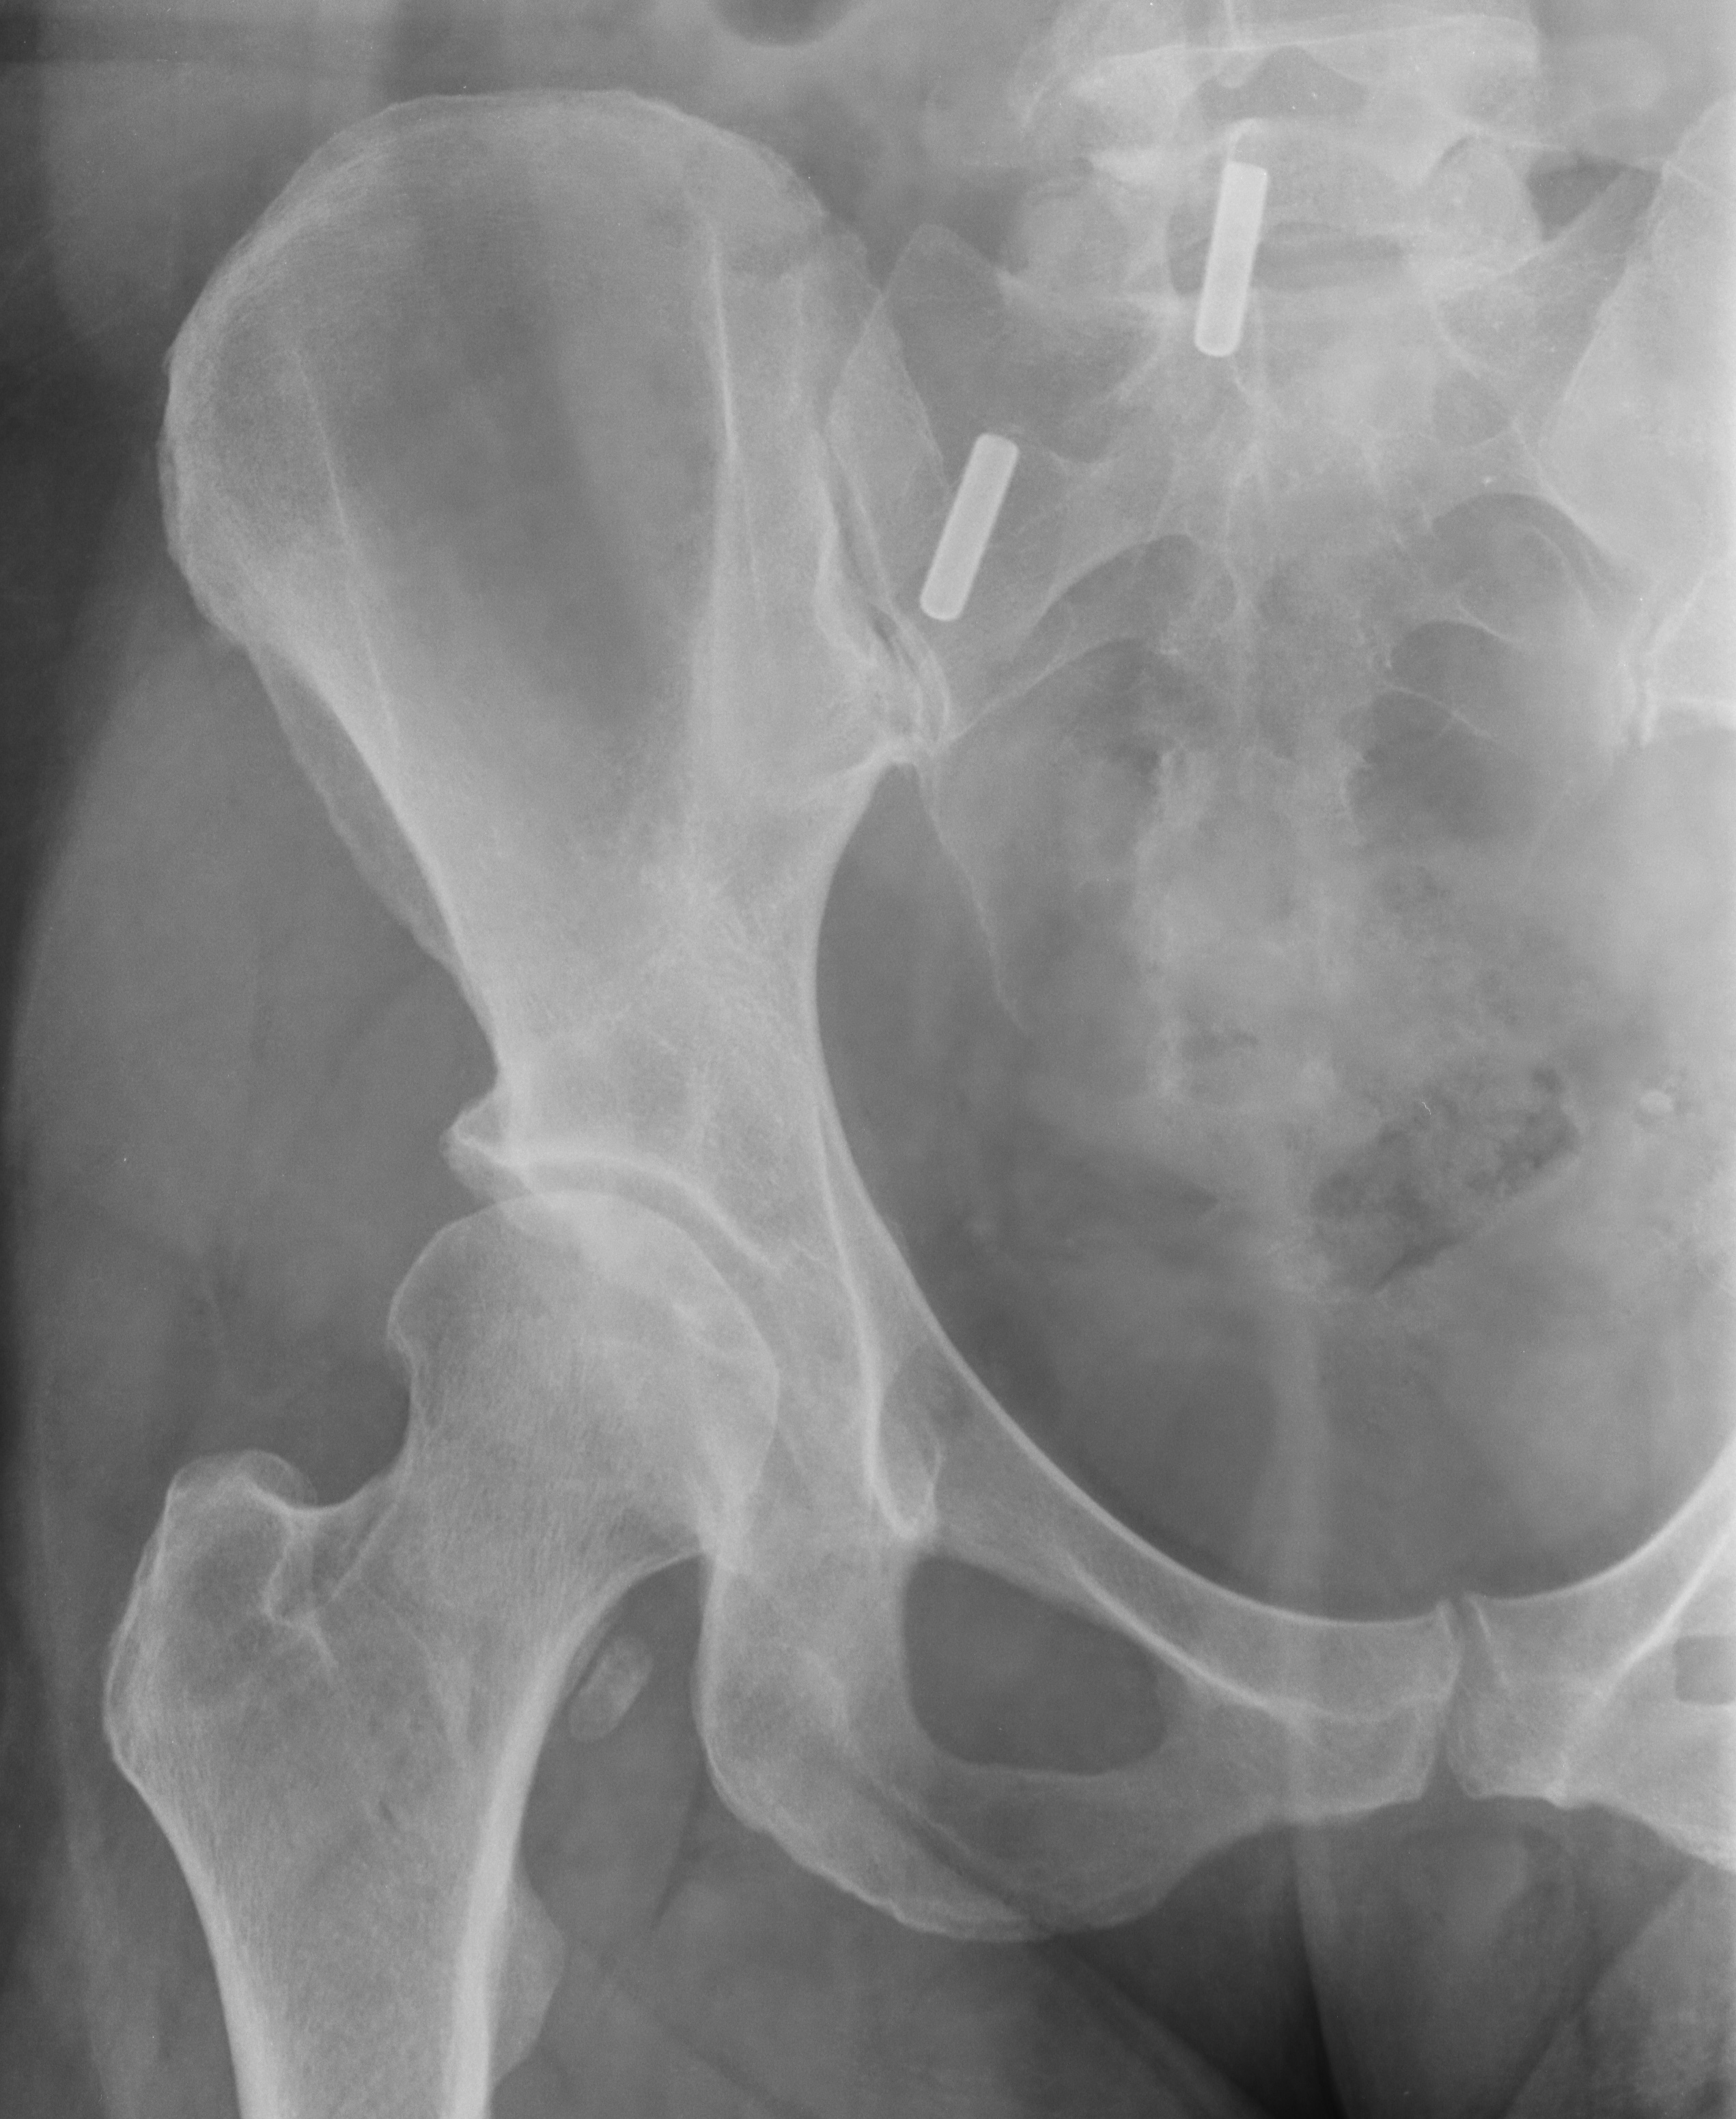

- Causes and Pathophysiology: Identifying the underlying causes and disease processes that contribute to hip pain.

- Diagnosis and Assessment: Employing appropriate diagnostic techniques and physical examinations to accurately assess the source and severity of hip pain.

Coxa is a comprehensive guide to understanding and managing hip joint pain. It provides detailed information on the causes of hip pain, including osteoarthritis, rheumatoid arthritis, and hip fractures. The book also discusses the various treatment options available for hip pain, including medication, physical therapy, and surgery. Coxa is an essential resource for anyone who is suffering from hip pain or wants to learn more about this condition.